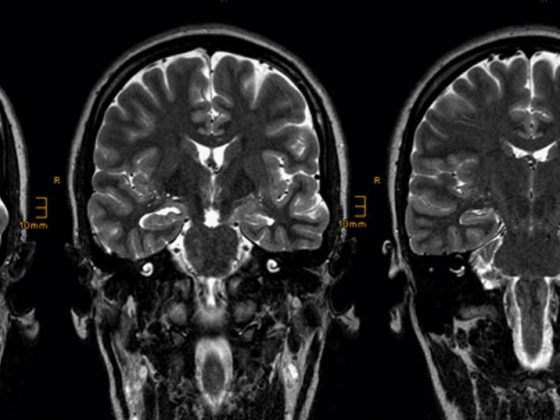

Was ist wichtig bei der Abklärung ­und Behandlung epileptischer Anfälle?

Etwa 5% aller Menschen erleiden in ihrem Leben­ einen epileptischen Anfall. Knapp 1% der Bevölkerung erkrankt im Laufe des Lebens an einer Epilepsie. In der Schweiz sind dies rund 70’000 Per­sonen, wobei die Inzidenz mit zunehmendem Lebensalter ansteigt.

epilepsie-mri_header

Übersicht zur MRI-Bildgebung